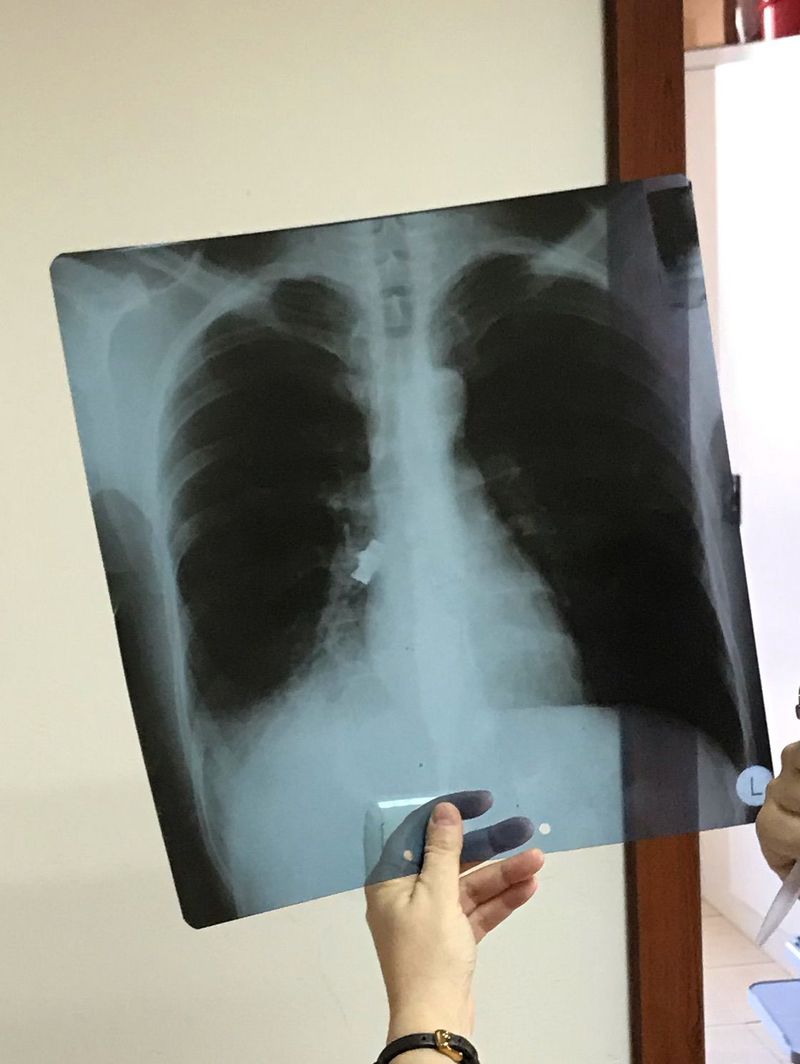

Bronchial foreign body

Undiagnosed and retained foreign bodies in lungs may result in serious complications such as pneumonia, atelectasis or bronchiectasis. We had this case in which he aspirated his 3 teeth bridge while sleeping (probably due to chronic alcohol intake).